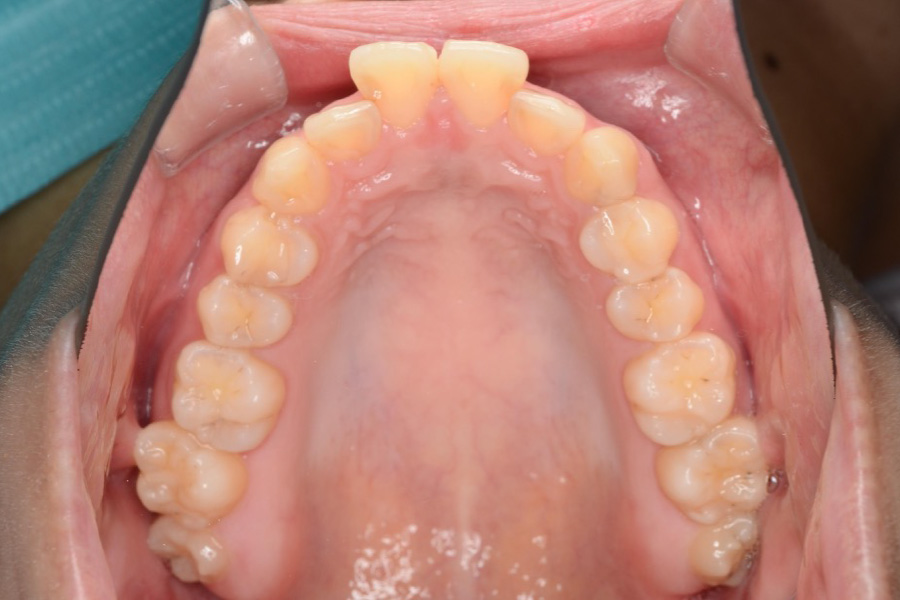

治療前